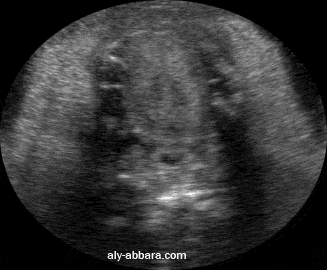

Ftus à 29 semaines d'aménorrhée

La cavité buccale vue par coupe transversale avec la mise en évidence des mouvements

de la langue et du pharynx buccal lors des déglutitions